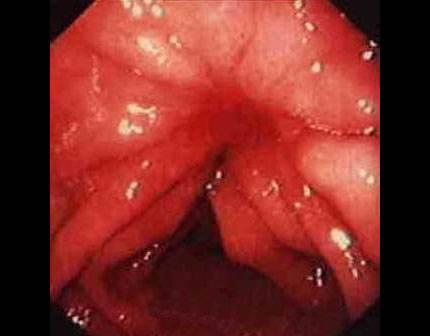

痔瘡癌變的10個(gè)前兆

1、痔瘡疼痛加劇:痔瘡患者如感覺疼痛逐漸加劇,可能是癌變的一個(gè)信號(hào)。

2、痔瘡出血:長期痔瘡出血,尤其是出現(xiàn)持續(xù)性出血時(shí),應(yīng)警惕癌變的可能。

5、肛門不適:出現(xiàn)肛門墜脹、異物感等癥狀時(shí),應(yīng)考慮痔瘡癌變的可能性。

9、肛周瘙癢:肛周瘙癢可能是痔瘡炎癥的表現(xiàn),長期不緩解可能發(fā)展為癌變。

10、便血顏色變化:如便血顏色由鮮紅色變?yōu)榘导t色或混合有黏液,應(yīng)引起重視。